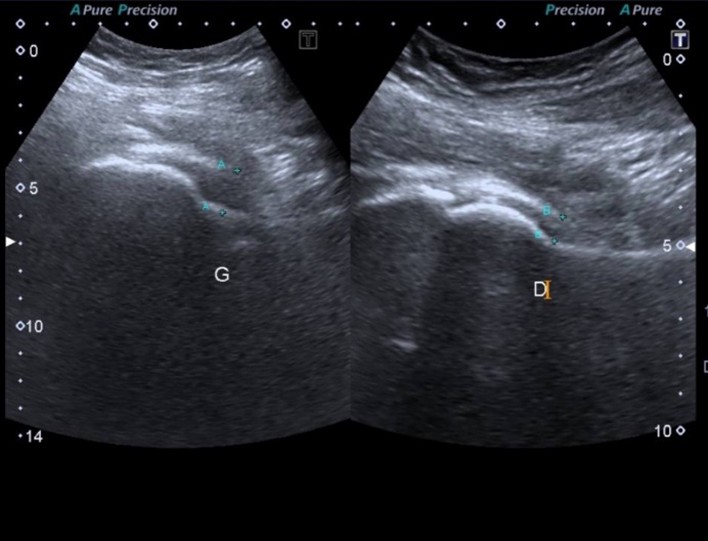

The initial laboratory findings: white blood cells (WBC) were 13.6×109/L (neutrophils: 11.83×109/L, lymphocyte count: 1.22×109/L), hemoglobin: 9 g/dL, normal glycated hemoglobin (HbA1c): 5.4%, platelet count: 81 ×109/L, erythrocyte sedimentation rate (ESR): 80 mm/hour and C-reactive protein (CRP): 12 mg/dL. Serum urea and creatinine were increased to 62 mg/dL and 1.8 mg/dL, respectively. Thyroid Stimulating Hormone was increased (TSH) at 6.6 mIU/mL (range: 0.35-5.1), normal free T4: 1.19 ng/dL (range: 0.5-1.4), normal free T3: 3.42 pg/ml (range: 1.8-4.2). The electrolytes and liver function tests were within normal range. The urinalysis showed bacteria 1+, red blood cells (RBC) > 100/HPF, WBC 38/HPF. In addition, the X-Ray of the left hip showed no bone/joint abnormality (Figure 3), whereas the ultrasound indicated an intra-articular collection around 16 mm (Figure 4).

Figure 3: Intra-articular collection of left hip joint

Figure 4: X-ray of left hip joint